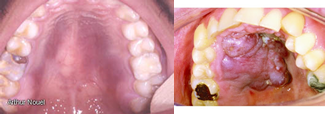

- Sarcoma de Kaposi; Es la neoplasia predominante en enfermos con SIDA, proceso neoplásico multifactorial, con lesiones en piel, ganglios linfáticos y vísceras. Las lesiones son muy numerosas, son maculas rosadas, rojas o violáceas y pápulas que formaran nódulos en la piel y mucosas.

Las lesiones orales pueden aparecer placas azuladas, plana en estadios iniciales que mas tarde se oscurecen y elevan que con frecuencia se ulceran. Se localiza principalmente en el paladar.